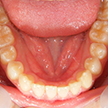

3. 術前下顎

下顎面観ではやはり右下1番の舌側転位、左下2,3番間の叢生が目立ちます。右下5番(第2小臼歯)が左側の同5番に遅れて萌出途中にあります。